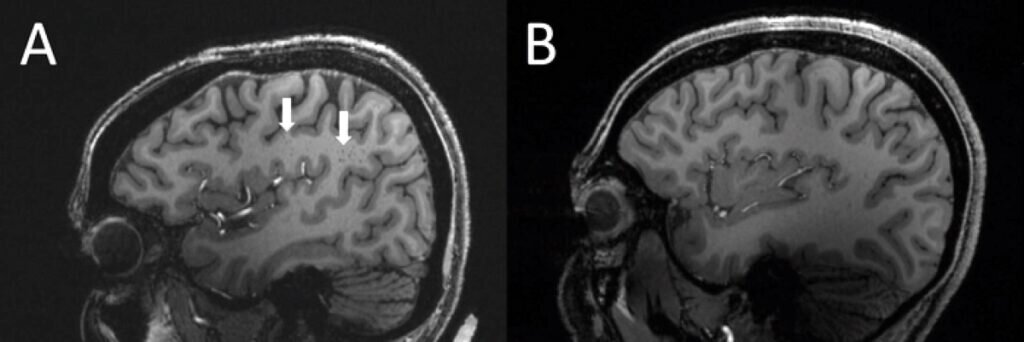

Слева — МРТ мозга пациента с мигренью; стрелками показана область полуовального центра с расширенными периваскулярными пространствами. Справа — МРТ здорового мозга / ©Wilson Xu, RSNA

Насим Шейх-Бахеи (Nasim Sheikh-Bahaei) и его коллеги обследовали десять добровольцев с классической мигренью и столько же страдающих от хронической мигрени, приступы которой сопровождаются аурой и случаются крайне часто. Контрольной группой выступили пять здоровых человек. В сравнении с ними у всех больных с мигренью периваскулярные пространства были расширены. Особенно заметно такое расширение оказалось в области полуовального центра — скопления белого вещества близ мозолистого тела, которое соединяет полушария друг с другом.

Расширение периваскулярных пространств считается важным диагностическим признаком повреждений мозга и неврологических заболеваний, включая некоторые виды деменции. Однако у больных мигренью подобное заметили впервые, и пока окончательно не ясно, как они связаны друг с другом. Периваскулярные пространства играют большую роль в очищении мозга от скапливающихся продуктов метаболизма. Возможно, их аномальное расширение свидетельствует о нарушении этой очистки, что и ведет к развитию мигрени. Но есть вероятность, что оно стало следствием более глубоких изменений — таким же симптомом, как сама головная боль.